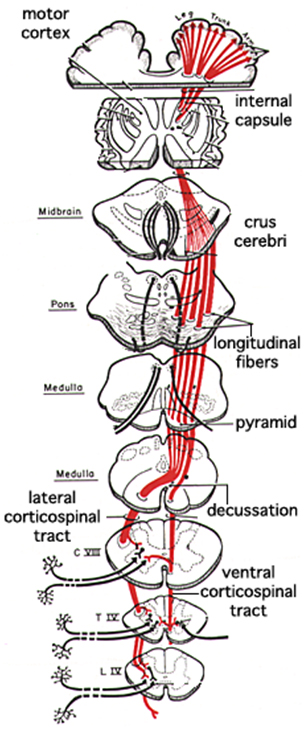

Пирамидная симптоматика в неврологии: ключевые аспекты

:background_color(FFFFFF):format(jpeg)/images/article/motor-cortex/XiebAmFl6VnmTW8eAak5Ww_thumbnail_T990_corticospinal_and_corticobulbar_tracts_PK.png)